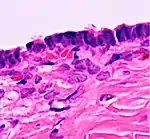

Histopathology

In case an ovarian cyst is surgically removed, a more definite diagnosis can be made by histopathology:

| Cystadenoma | Serous cystadenoma | Cyst lining consisting of a simple epithelium, whose cells may be either:[19]

|